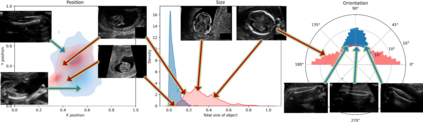

Fetal growth assessment from ultrasound is based on a few biometric measurements that are performed manually and assessed relative to the expected gestational age. Reliable biometry estimation depends on the precise detection of landmarks in standard ultrasound planes. Manual annotation can be time-consuming and operator dependent task, and may results in high measurements variability. Existing methods for automatic fetal biometry rely on initial automatic fetal structure segmentation followed by geometric landmark detection. However, segmentation annotations are time-consuming and may be inaccurate, and landmark detection requires developing measurement-specific geometric methods. This paper describes BiometryNet, an end-to-end landmark regression framework for fetal biometry estimation that overcomes these limitations. It includes a novel Dynamic Orientation Determination (DOD) method for enforcing measurement-specific orientation consistency during network training. DOD reduces variabilities in network training, increases landmark localization accuracy, thus yields accurate and robust biometric measurements. To validate our method, we assembled a dataset of 3,398 ultrasound images from 1,829 subjects acquired in three clinical sites with seven different ultrasound devices. Comparison and cross-validation of three different biometric measurements on two independent datasets shows that BiometryNet is robust and yields accurate measurements whose errors are lower than the clinically permissible errors, outperforming other existing automated biometry estimation methods. Code is available at https://github.com/netanellavisdris/fetalbiometry.